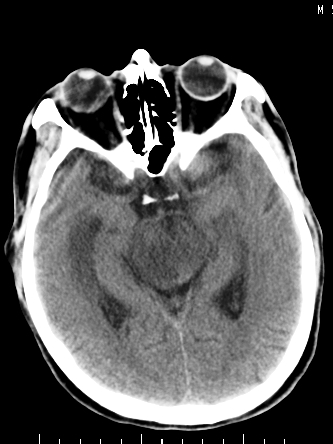

m/50,头昏头痛1月,近3天感觉左半肢体活动不利,自述半年前呈患肺tb,腰穿脑脊液未见特殊改变。现做头颅ct请大家会诊。

考虑颅内感染性病变:结核可能性大。

结核性脑膜炎,结核瘤,梗塞灶三症并存,提示颅内结核感染可能性大。

感染性病变;脑干脓肿(脓肿壁形成期),基底节及内囊(脑炎期)。顺便问一句,该病人是不是抵抗力很差,有没有糖尿病。

右侧基底节区缺血性脑梗塞.脑干区考虑结核.